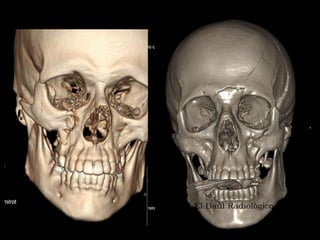

CONFIGURACION

EXTERNA

VISTA LATERAL VISTA INFERIOR

VISTA ANTERIOR

CABEZA OSEA CARACTERISTICAS:

• CRANEO:

– Calota o Bóveda craneana

– Base del Cráneo

• CARA:

• CAVIDADES EN CRANEO Y CARA

• Cavidad Orbitaria

• Fosas nasales

• Fosa Pterigoidea

• Fosa Ptérigomaxilar

• Fosa Cigomática

• Fosa Temporal

• Cavidad Oral

• Bóveda Palatina

• Articulaciones Inmóviles: Suturas

• Agujeros y fisuras